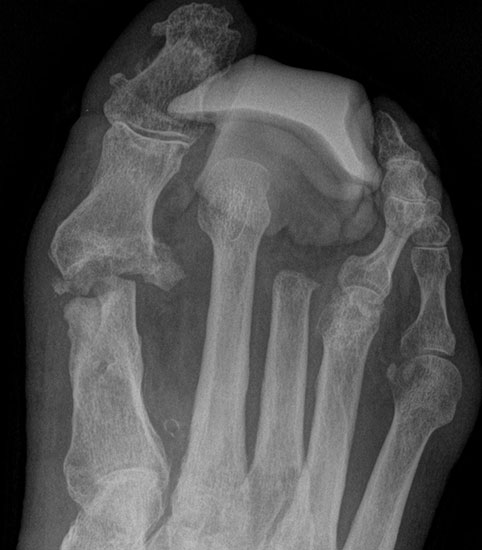

Exartikulationen im Großzehengrundgelenk bedingen bei Neuropathie häufig Druckulze­rationen am Metatarsalekopf (Abb. 6, 7). Wenn vertretbar, wird die Basis des Grundglieds mit den Sehnensansätzen erhalten, um chronische Druckprobleme zu vermeiden (Abb. 8). Im Falle einer Exartikulation ist dem Druck unter dem Metatarsale-I-Kopf große Aufmerksamkeit zu widmen. Durch eine Entfernung der Sesambeine und Abtragen von plantaren knöchernen Prominenzen kann die Auflagefläche vergrößert und damit der Druck reduziert werden. Postoperativ muss der Mittelfuß durch Einlagen in seinem Gewölbe breitflächig abgestützt werden (Abb. 9). Ansonsten resultiert ein Plattfuß mit Pronation und Abduktion.

Amputation im 1. Mittelfußknochen

Wir bevorzugen die Amputation im Mittelfußknochen gegenüber der Exartikulation im MTP Gelenk (Abb. 10): Ein Ulkus an dem Metatarsale I Stumpf ist durch stützende Einlage zu verhindern.

Tennisschlägerartige Umschneidung der Großzehe (Abb. 11). Das Metatarsale wird so osteotomiert, dass an der Medial- und Plantarseite keine Knochenkanten verbleiben (Abb. 12).

Wird das Metatarsale I im Schaftbereich abgesetzt, muss der Fuß analog zur Amputation im Grundglied zur Verhinderung eines Plattfußes bzw. eines Druckulkus am Stumpfende medial langstreckig gut abgestützt werden (Abb. 9). Die Einlegesohle muss einen integrierten Platzhalter aufweisen, um die Varuskippung der 2. Zehe zu verhindern.